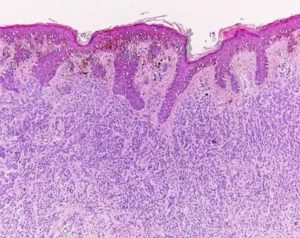

7. Окрашивание материала. Это необходимо, чтобы различить под микроскопом различные клетки и ткани. В неокрашенном материале все структуры преломляют свет одинаково и рассмотреть ничего не удастся.

- Микроскопическое исследование. Гистолог с помощью оптического прибора изучает полученную пластинку.

- Исследование под микроскопом. Самый важный этап диагностики. При помощи современных оптических приборов лаборант исследует полученные пластины и записывает данные для передачи лечащему врачу. Результаты максимально точные и достоверные.

Для приготовления срезов используют специализированную технику – ультрамикротомы для осмотра в электронных микроскопах или микротомы для изучения образца в световом оборудовании.

- Световая – классические микроскопы с различной степенью увеличения.

- Ультрафиолетовая – с использованием лучей ультрафиолетовой части спектра. Невидимые при обычном освещении дефекты клетки, среза становятся видимыми.

- Флюоресцентная – исследование проводят с использованием ртутных, ксеноновых ламп.

- Фазово-контрастная – применяется при неэффективности других методов исследования образцов. Ткани предварительно окрашивают.

- Электронная – образец облучают потоком электронов. Преимуществом способа является многократное увеличение, высокая разрешающая способность оборудования.